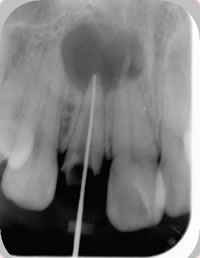

治療方法は、まず根管治療で感染した歯の内部を清掃し、無菌的な状態にします(図2)。

図2 根管治療で根管内の清掃と無菌化を行う.その後、歯根端切除の手術をする